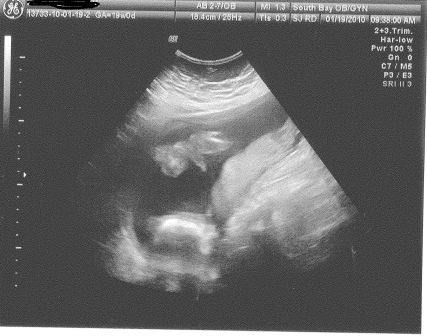

sonogram pic- Boy or Girl?

What does this look like to you? The sonogram tech pointed to that and said it was a boy. The more I look at it the less convinced I am. It looks too pointy and long to be a penis. It could be the umbilical cord or something else. My friend thinks it's a thigh bone. Plus there are no testies.

I just want to make sure before I register and paint the nursery.

You are 22wks...right?

to me thats an obvious penis.

Its the butt...I can make the sono out.

IDK what it is, that doesn't look like my boy sono. (pics in album) I would hold off on paint until you know 100%.

Yes, I'm 22 weeks. Should I expect to see testies at this point? I don't see any.

The sono isn't very easy to make out, but it looks like a hot dog. A girl has a hamburger. Looks like a pee pee to me!

it's a ...the pic is of his butt like looking up from the floor if that helps...legs on either side

here's our pic...a little clearer but same angles just flipped over Image Attachment(s):

Yup! Looks just like the one above! All boy!